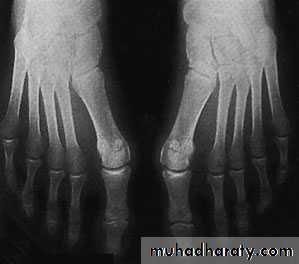

Hallux valgus:

It’s the commonest foot and musculoskletal deformity seen in practice.There is valgus deviation of the big toe with mild medial rotation where the nail facing slightly to the medial side, there is also overcrowding of the other toes with the 2nd. Toe usually develops the deformity known as hammer toe (extension of the metatarsophalangial joint, flexion of the proximal interphalangial and extension of the distal interphalangial joint).

X-ray:

Taken with the patient standing to show the degree of metatarsal and hallux angulations.Also it shows the state of the joint being normal, arthritic or subluxated.